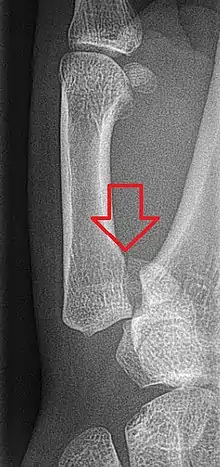

Bennett fracture on x-ray

Bennett fracture is a type of partial broken finger involving the base of the thumb, and extends into the carpometacarpal (CMC) joint.[1]

This intra-articular fracture is the most common type of fracture of the thumb, and is nearly always accompanied by some degree of subluxation or frank dislocation of the carpometacarpal joint.